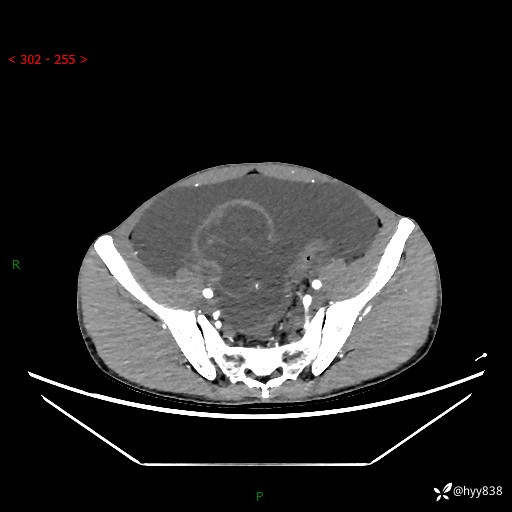

现病史:患者10天前无明显诱因出现腹部胀痛不适,无畏寒发热,无胸痛胸闷,无心慌气短,无恶心呕吐,无腹泻及黑便,无粘液血便及里急后重等症状,4天前在当地县人民医院就诊,行腹部CT示:下腹部占位性病变,腹腔及盆腔积液;今患者为求进一步诊治来我院治疗,门诊以“腹水”收治入院。 发病以来,精神饮食可,大小便正常,体重体力无明显变化。

腹部CT平扫+增强